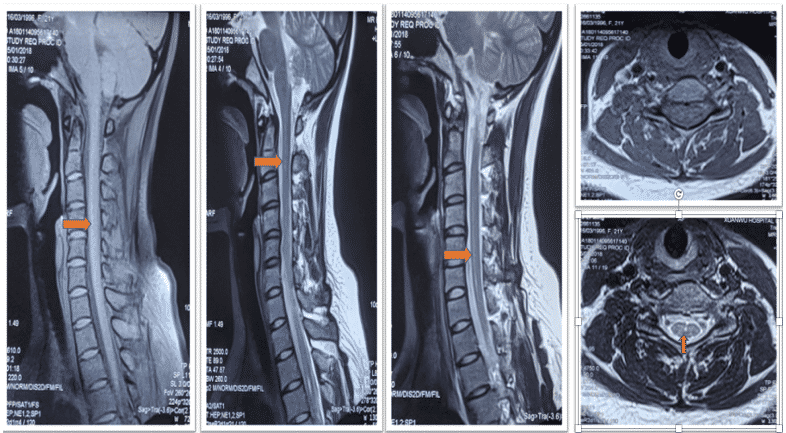

颈髓&胸髓MRI+增强(2018-1-15首都医科大学宣武医院):颈椎曲度变直;C2-6椎体水平龍内异常信号影,考虑轻度中央管扩张;T3椎体水平信号异常,考虑中央管扩张可能。

脊髓空洞症

中央管扩张是脊髓空洞症早期影像学表现,临床诊断一定注重临床象!